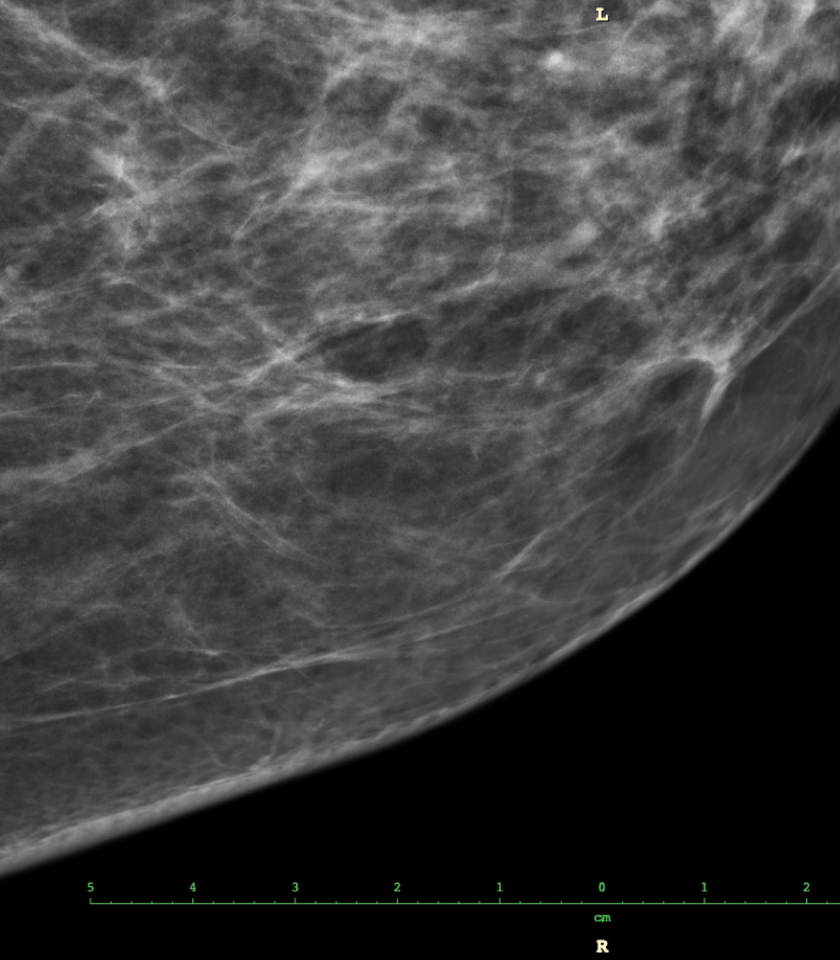

Genetika, obezita, alkohol, to jsou všechno faktory, které riziko rakoviny prsu zvyšují a ženy si je velmi dobře uvědomují. Existuje ale jedna věc, kterou si mnoho lidí s vyšším výskytem rakoviny prsu primárně nespojuje a to je hustota prsní tkáně.

Jak ukázal nový výzkum, většina žen si je vědoma různých rizikových faktorů. Mezi ně patří onemocnění rakovinou prsu v rodině, nástup menopauzy či první menstruace před 11. rokem, alkohol, stres, obezita, nevhodná strava, žádné nebo pozdní těhotenství i prodělaná biopsie prsu, hormonální léčby či ozařování. Existuje ale jeden neméně závažný rizikový faktor, který podle výsledků studie drtivá většina žen opomíjí. A tím je hustota prsní tkáně.

O tom, že hustá prsní tkáň může představovat o 1,2 až 4 % vyšší riziko rozvoje rakoviny prsu, vědělo jen 6 z 61 dotazovaných žen. Většinu z nich na to, že mají vysoký podíl husté prsní tkáně, přitom upozorňovali lékaři během mamografu. Čím je totiž hustota prsní tkáně větší, tím je navíc obtížnější na mamografickém snímku zhoubný nádor či jiné změny objevit.

Vysoká denzita prsní tkáně (nebo též mamografická denzita) představuje zvýšené riziko vzniku rakoviny prsu; podle výsledků dalšího výzkumu však pacientkám s rakovinou prsu, které mají vysokou mamografickou denzitu, nehrozí zvýšené riziko úmrtí na toto onemocnění. Výsledky výzkumu, který vedla dr. Gretchen L. Gierachová z amerického Národního onkologického ústavu (National Cancer Institute, NCI) a který se uskutečnil ve spolupráci s odborníky z Breast Cancer Surveillance Consortium (BCSC), byly publikovány v odborném časopise Journal of the National Cancer Institute.